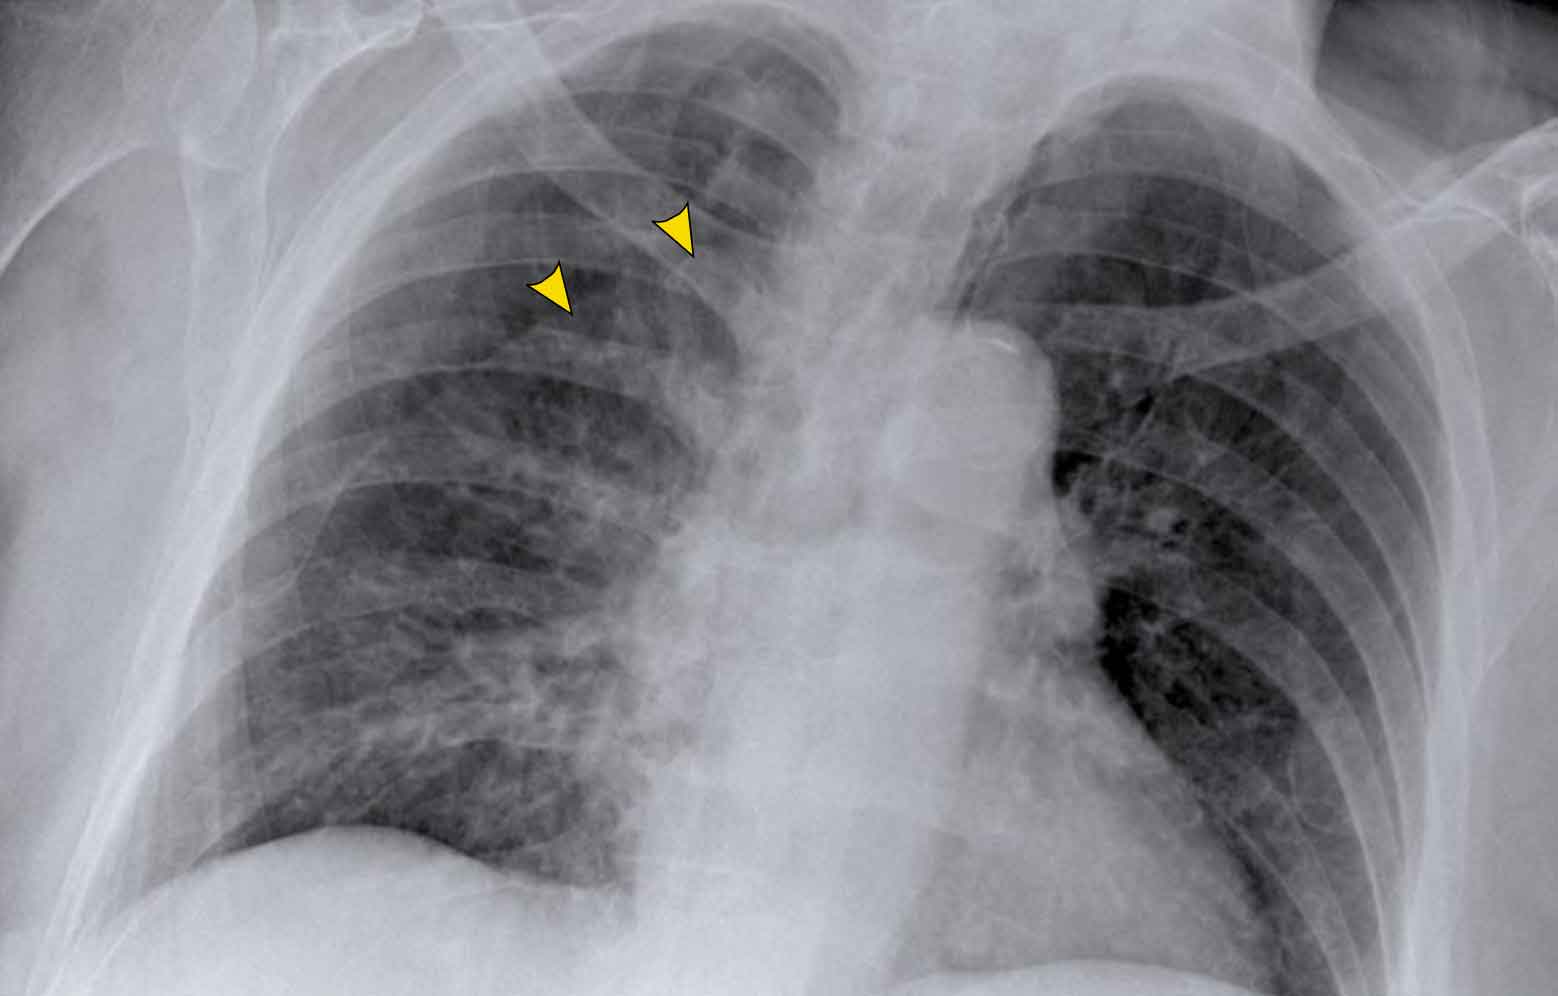

Case 2 – Cystic Lung Disease with Hydropneumothorax

- Chest X-ray- Mediastinal shift to the left

- Air-fluid level (hydropneumothorax) (black arrow)

- Upper lobe adhesions to the chest wall. Maybe this patient was treated for a prior pneumothorax.

- Lung cyst in the right upper lobe (yellow arrowhead)

Conclusion

We are dealing with a woman with a cystic lung disease, who probably had prior pneumothoraces.

The most likely diagnosis is lymphangioleiomyomatosis (LAM), a rare cystic lung disease involving proliferation of smooth muscle, leading to airway obstruction, pulmonary cysts, and recurrent pneumothoraces.

LAM can occur sporadically or in association with tuberous sclerosis complex (TSC).